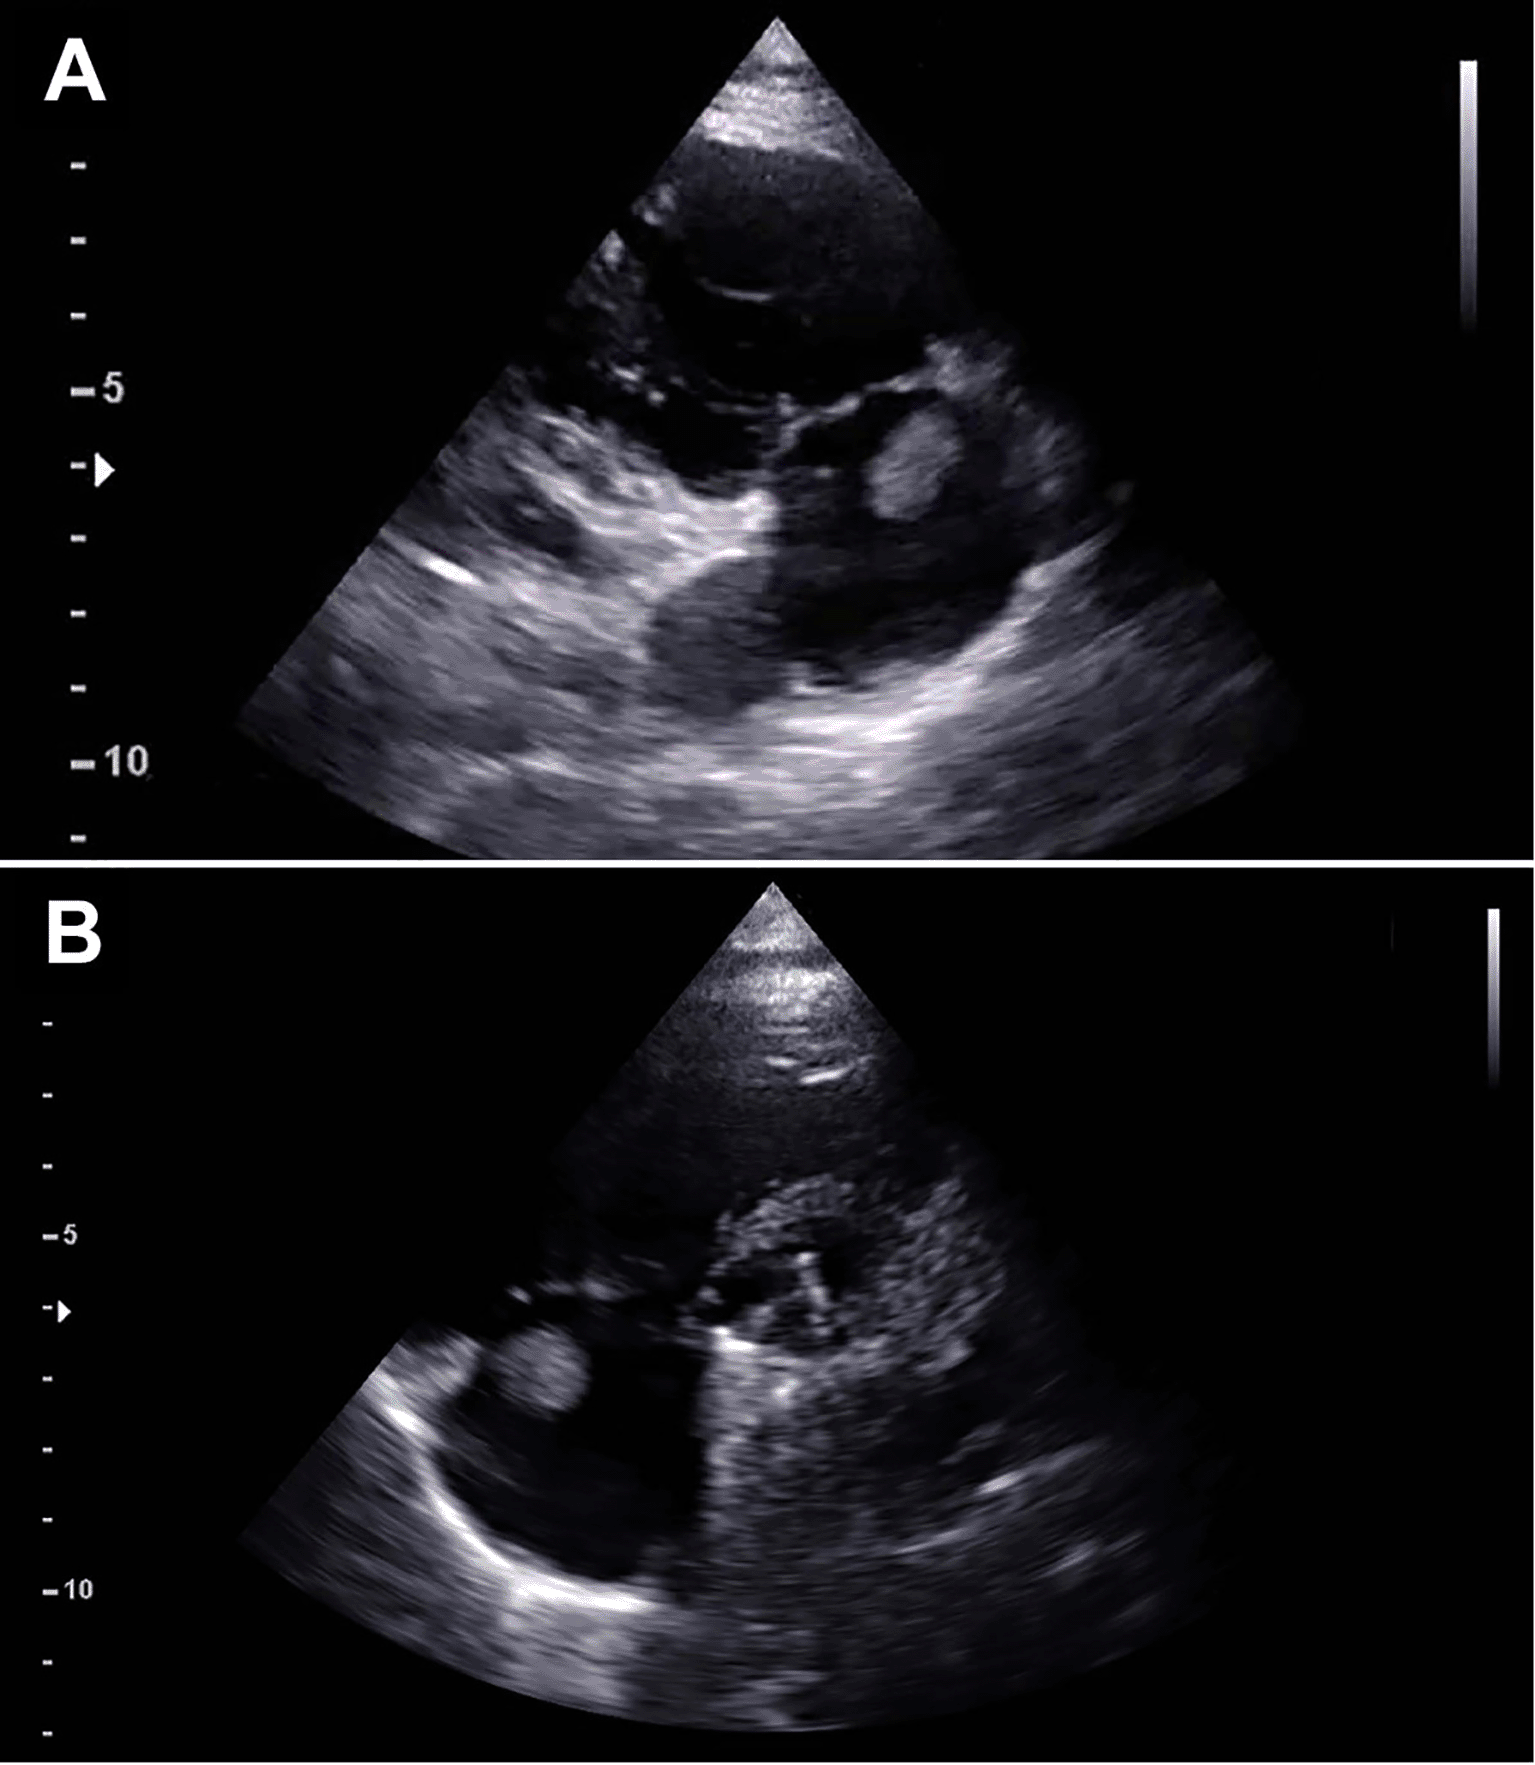

At the follow-up visit 41 months after surgery, the TTE showed a mobile mass measuring 10 x 15 mm and arising from the atrial wall just above the tricuspid annulus (Figure 1). The right atrium was normal in size and structure (diameter: 31 mm; area: 15 cm2). The mass appeared mobile with the cardiac cycle, but no interference with the tricuspid valve function was noticed. Surgical indication was given based on the significant dimension of the mass, its position close to the tricuspid valve, the risk for embolization and the possible neoplastic nature.

Preoperative echocardiography demonstrating a mass measuring 11×12 mm attached at the junction of the right atrium and tricuspid annulus as shown in the right ventricle inflow view (A) and parasternal short axis view (B).